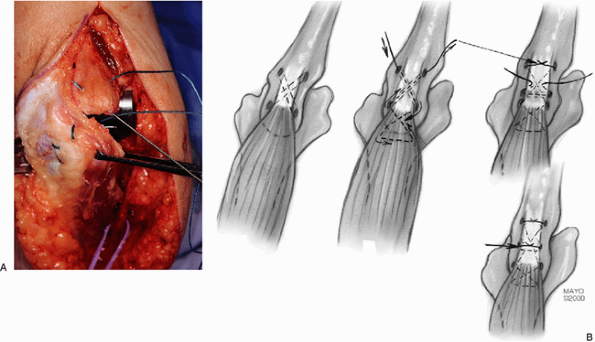

pathology dictates this. The proximal ulna is prepared for reattachment

of the triceps by placing drill holes obliquely both medially and

laterally in a cruciate fashion (Fig. 18-35A,B). A third transverse hole is placed across the proximal ulna (Fig. 18-35C).

A heavy nonabsorbable (No. 5) suture is then brought through the distal

medial hole with a Keith needle. The elbow is placed in 90 degrees of

flexion and the triceps is reduced over the tip of the olecranon. The

suture is then inserted in the triceps at this point and a criss-cross

stitch is placed in the triceps tendon (Fig. 18-36).

The suture then penetrates from the tendon medially and is directed

obliquely through the second hole to emerge on the lateral aspect of

the ulna. The suture is then brought through the forearm and ulnar

periosteum in such a way as to meet the initial suture on the medial

aspect of the ulna and is tied off the subcutaneous border (Fig. 18-36). A transverse suture is then placed across the ulna and through the tendon to further stabilize the attachment.

![]() |

|

Figure 18-35. Cruciate (A,B) and transverse (C) drill holes are placed in the proximal ulna.

Figure 18-36. A,B:

The sutures have been placed through the ulna and in a criss-cross fashion in the tendon. The elbow is at 90 degrees of flexion when these sutures are tied. |